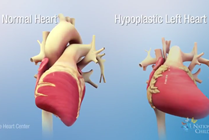

Hypoplastic Left Heart Syndrome

Hypoplastic left heart syndrome (HLHS) is a congenital heart defect where most of the structures on the left side of the heart are small and underdeveloped. The Hybrid approach, developed by surgeons at Nationwide Children's Hospital, is an alternative to Norwood open heart surgery for HLHS.